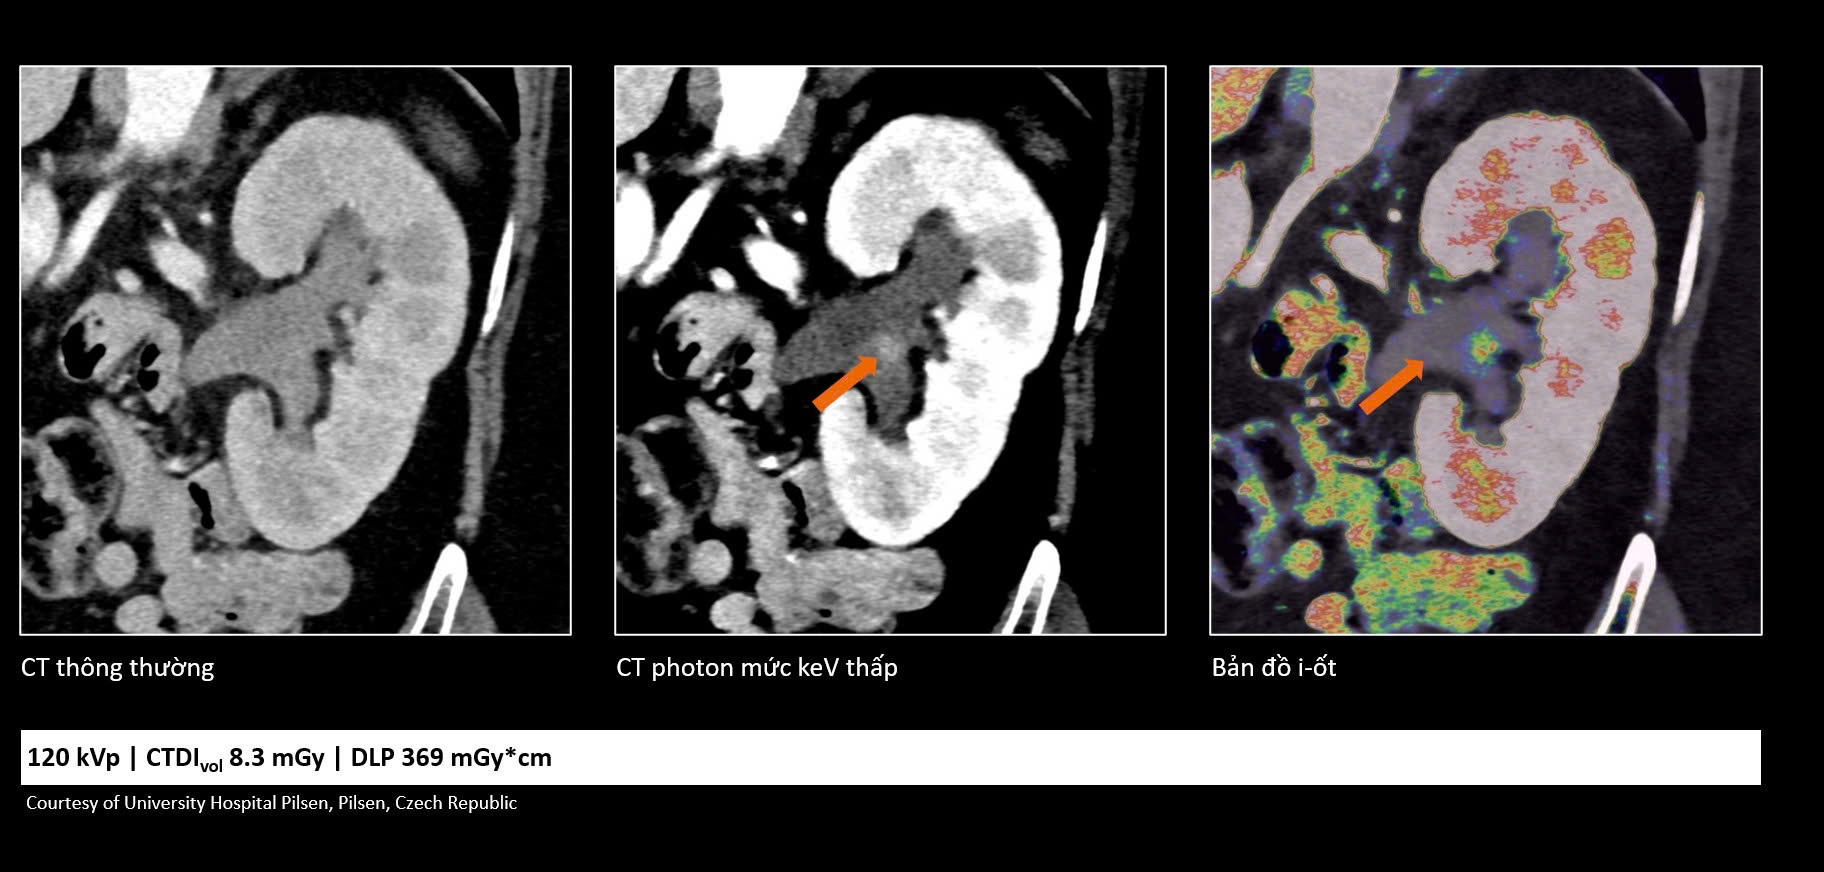

Theo chia sẻ tại hội nghị, các hệ thống CT hiện đại ngày nay đã trở thành công cụ quan trọng trong phát hiện và theo dõi nhiều bệnh lý. Tuy nhiên, với những ca bệnh phức tạp, hình ảnh CT truyền thống đôi khi vẫn bị nhiễu hoặc thiếu chi tiết, gây khó khăn trong việc đánh giá chính xác đặc điểm tổn thương.

Sự xuất hiện của công nghệ cắt lớp vi tính lượng tử mang đến một hướng tiếp cận hoàn toàn mới. Trước đây, CT chủ yếu cung cấp thông tin về hình thái như kích thước, hình dạng hay cấu trúc tổn thương. Nhưng với công nghệ mới, nhờ khả năng ghi nhận trực tiếp các photon tia X đi qua cơ thể, hệ thống có thể cung cấp thêm nhiều dữ liệu giá trị về bản chất của tổn thương.

Những thông tin này không chỉ giúp bác sĩ quan sát rõ hơn về mặt hình ảnh, mà còn hỗ trợ đánh giá sâu hơn về đặc tính sinh học, từ đó hiểu rõ tình trạng bệnh của từng bệnh nhân và đưa ra quyết định điều trị chính xác hơn.

Nhờ cải thiện độ tương phản hình ảnh, CT lượng tử giúp nhận diện sớm các vùng nhồi máu hoặc vi xuất huyết, đồng thời phân biệt chính xác với chất cản quang. Bên cạnh đó, khả năng giảm nhiễu kim loại sau can thiệp cũng giúp bác sĩ đánh giá rõ ràng hơn tình trạng mạch máu, nâng cao độ tin cậy trong chẩn đoán.